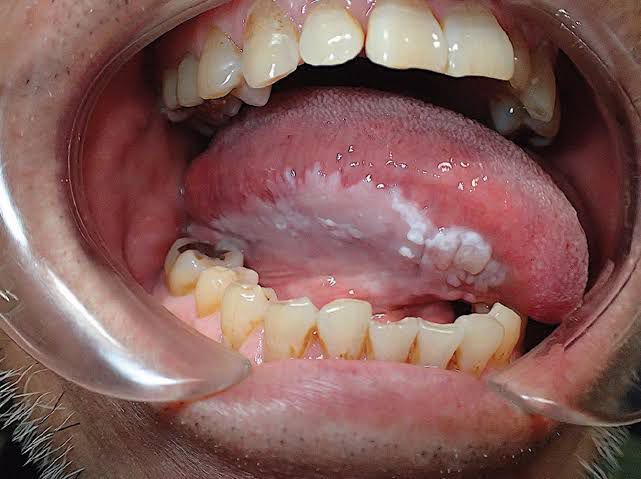

Leukoplakia

Leukoplakia is a condition in which one or more white patches or spots (lesions) forms inside the mouth. Leukoplakia is different from other causes of white patches such as thrush or lichen planus because it can eventually develop into oral cancer.